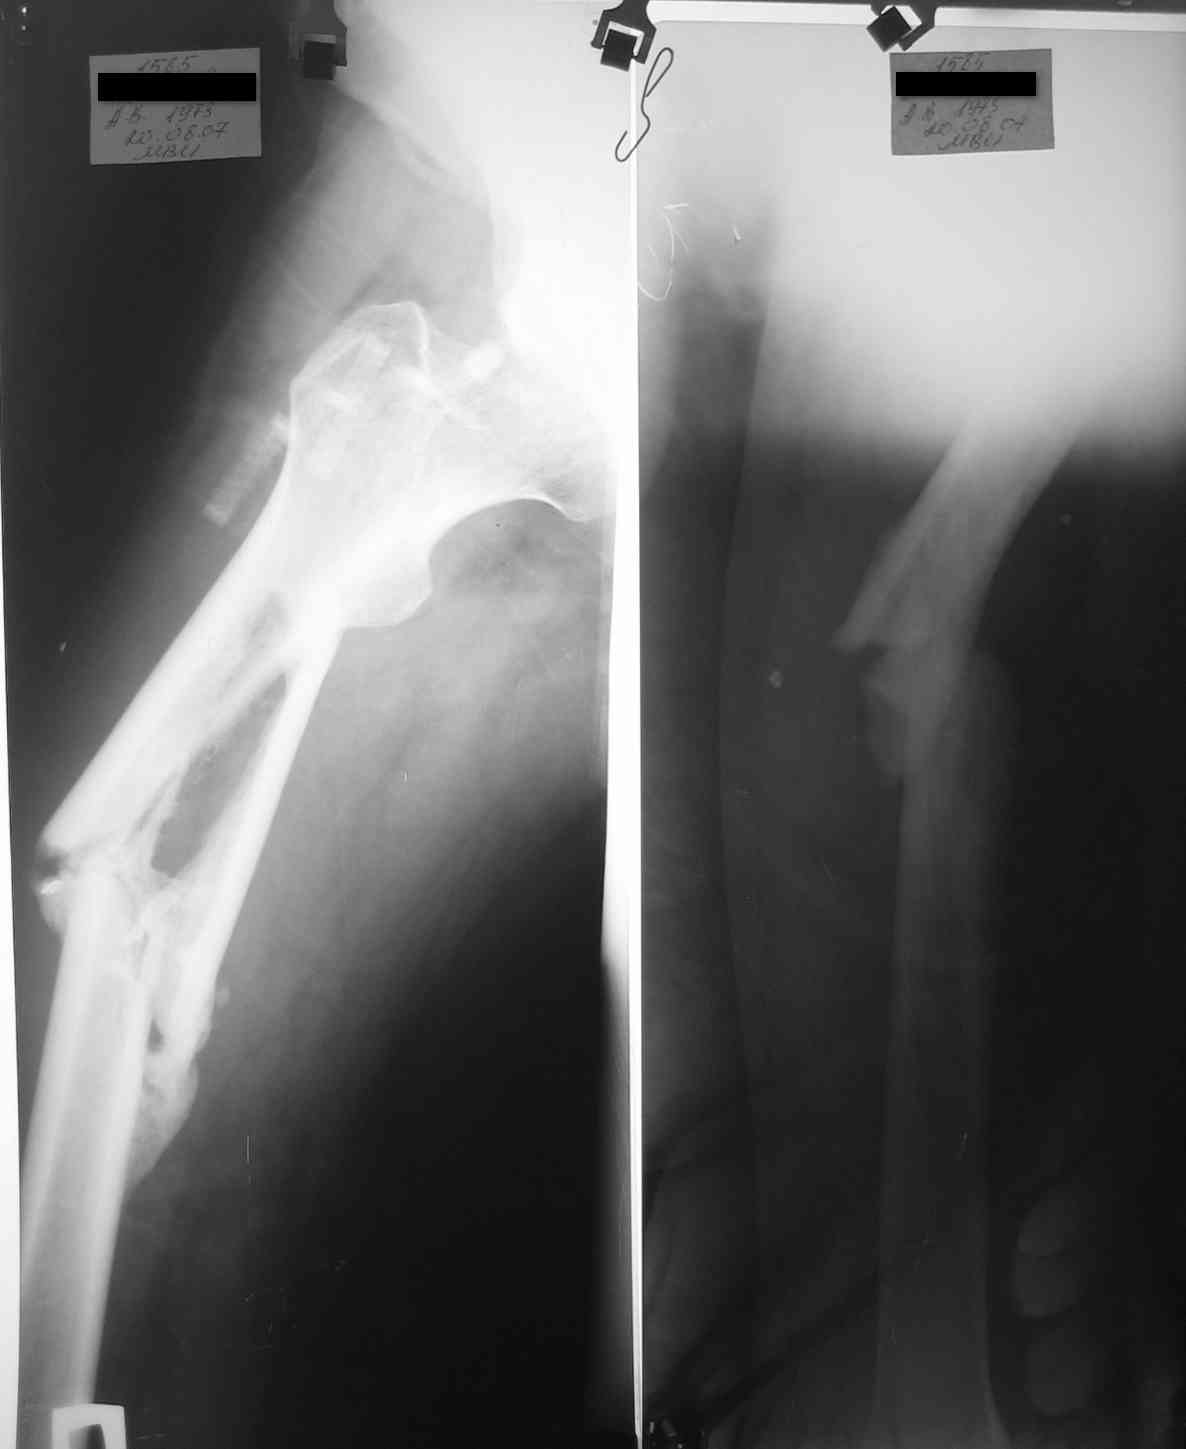

уважаемые коллеги, поступил пациент, через 6 месяцев после травы, который лечлся скелетным вытяжением на районе 3 месяца

затем гипс еще 1,5 месяца, дозированная нагрузка через 3,5 месяца после травмы. Дней 5 назад поскользнулся в ванной, почувствовал боль в бедре, появилась деформация. Оперирован у нас, произведен остеосинтез блокирующим стержнем ,перелом не открывался, был "доломан" на столе. меня интересует вариант вальгирования гвоздя в этом случае. И по-вашему какие ерспективы у этого клиента?